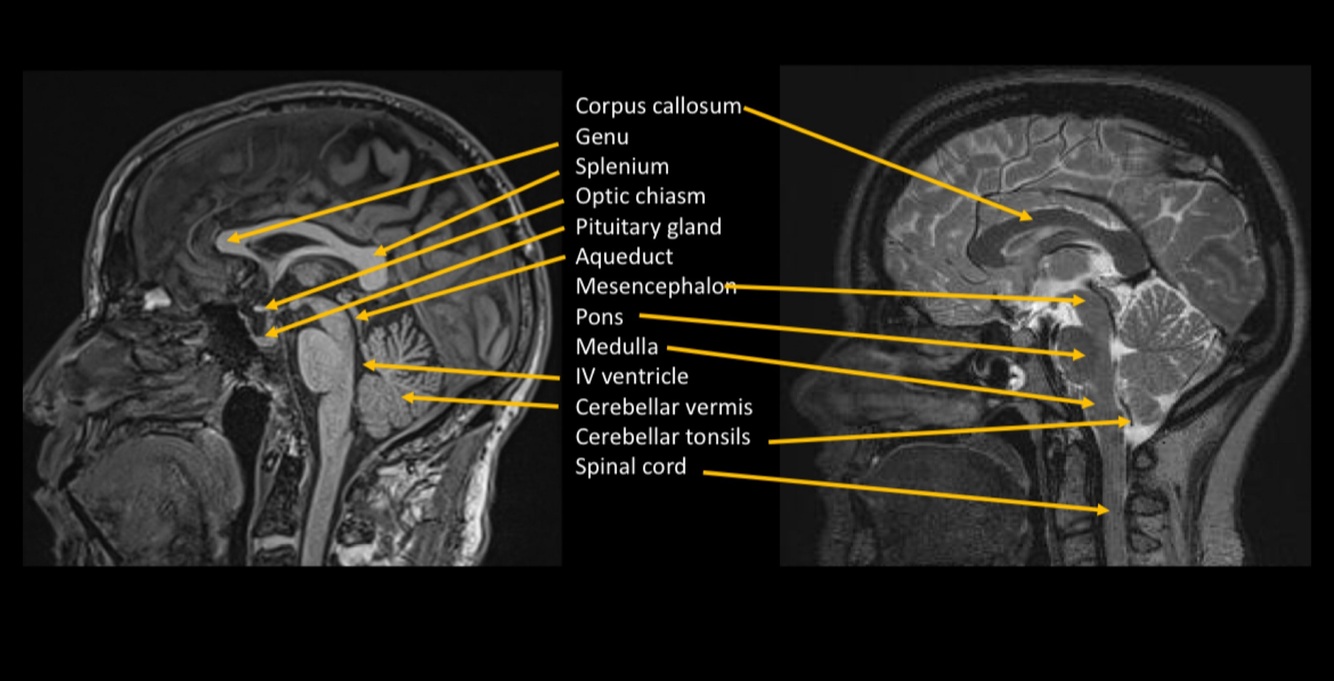

¿Qué técnica observamos?

RESONANCIA MAGNÉTICA